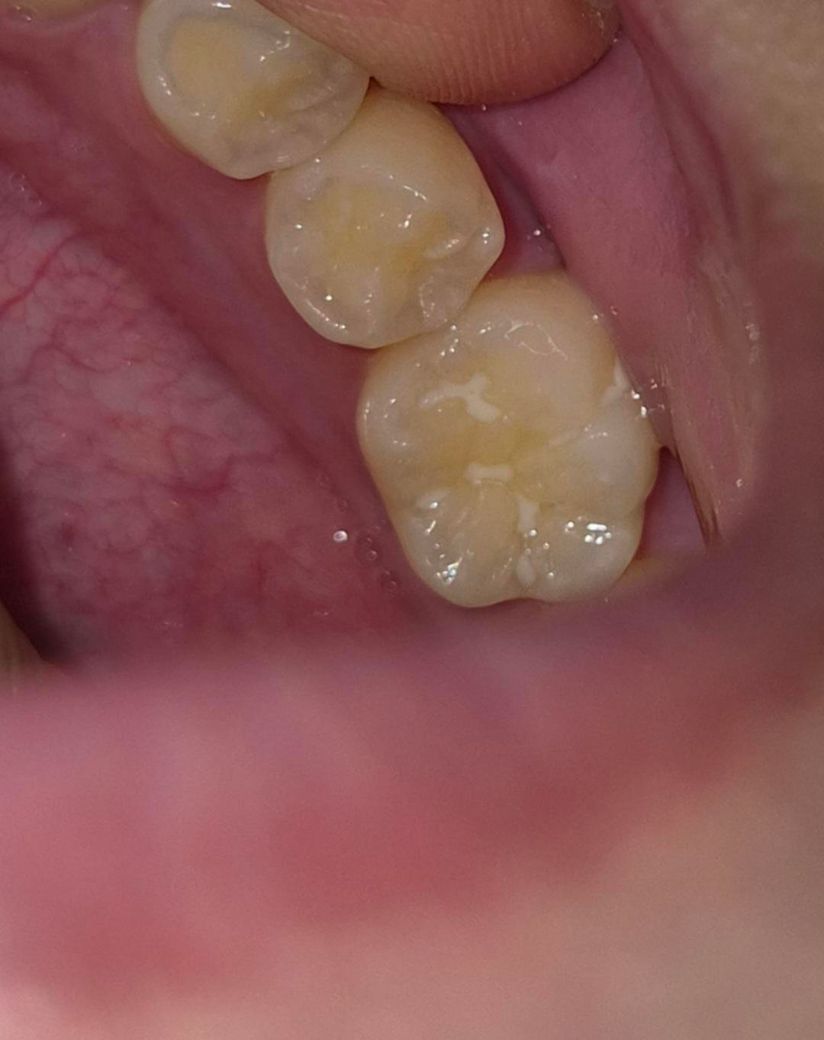

아이 어금니 실란트 떨어진 부위? 충치인건지요

어금니 동그라미친 부분인데요 , 실란트가 부분부분 삭제되긴했어요 근데 유독 저부분만 뒤쪽이긴하지만 각도때문인건지 신경쓰여서요 치과에서는 충치는아니고 실란트가 떨어져서 그렇고 빛에따라서 음영? 암튼 눈으로보면 뭐가껴있거나 그런식으로 색이 보여질수는있다고, 치과빛으로비춰 거울로보고 검진해도 충치는아니라고하셨는데 .. 왤케신경이 쓰이는건지.. 제가 어떤각도에서보면 유독저부분이 진짜뭐가껴있거나 충치같은색으로 보이기도하고 또어떤각도에선 괜차나보이기도하고 그러긴해요 ㅜㅜ 다른전문가분들의 의견이궁금합니다